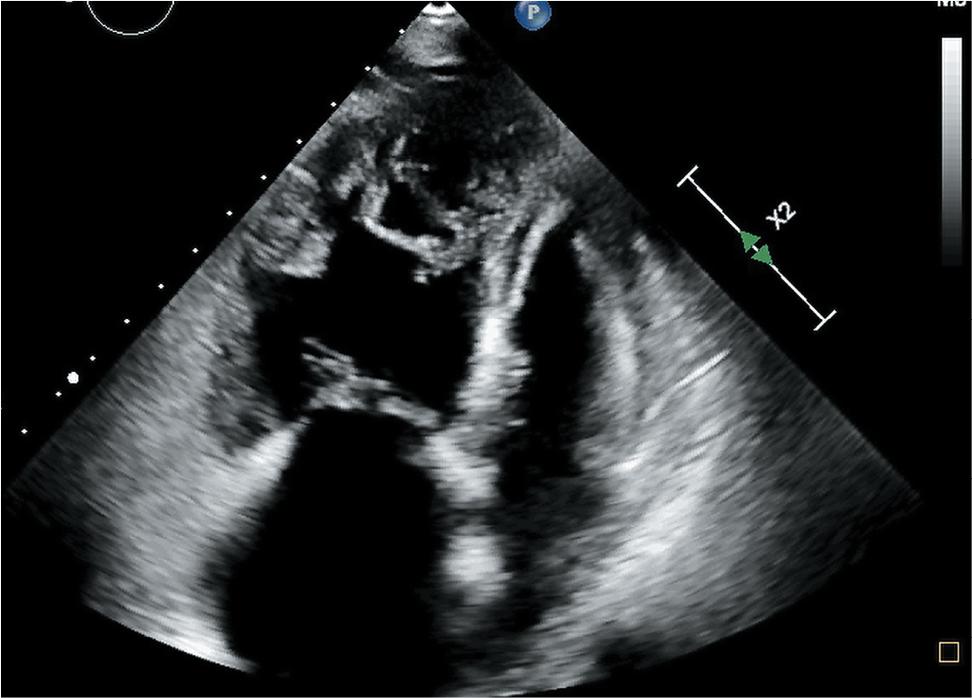

Blood tests showed polycythaemia and a mildly increased N-terminal pro B-type natriuretic peptide (NTproBNP) of 677 pg/mL. Pulmonary function tests showed normal respiratory volumes and flows, but with a moderately low diffusion lung capacity for carbon monoxide (DLCO) of 49% predicted. The electrocardiogram showed an aspect of right ventricular strain and an incomplete right bundle branch block. A cardiac ultrasound was performed that showed dilation of the right heart, with a RA (right atrium) of 74 mm and a RV (right ventricle) of 40 mm, a low TAPSE (Tricuspid Annular Plane Systolic Excursion) of 16 mm, global right ventricular systolic dysfunction, severe tricuspid regurgitation, a RA-RV gradient of 80 mmHg, with a high probability of PH, an estimated sPAP (Systolic Pulmonary Artery Pressure) of 85 mmHg. Left ventricular structure and function were normal, and no pericardial effusion was detected (Figure 2).

Cardiac ultrasound: dilation of the right heart, with a high probability of PH. PH, pulmonary hypertension.